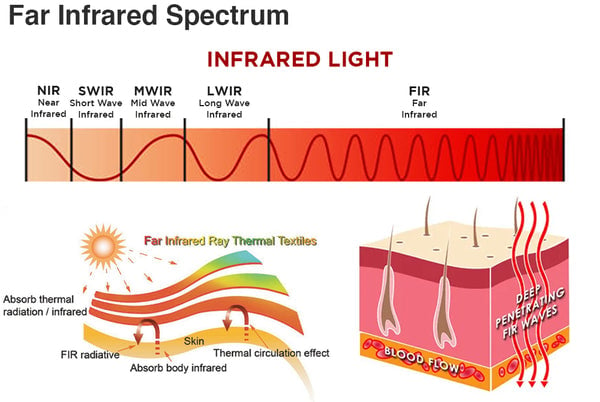

האם החום ניתן לכוונון?

לא, החום נוצר באופן טבעי על ידי חלקיקי טורמלין במגע עם עורכם.